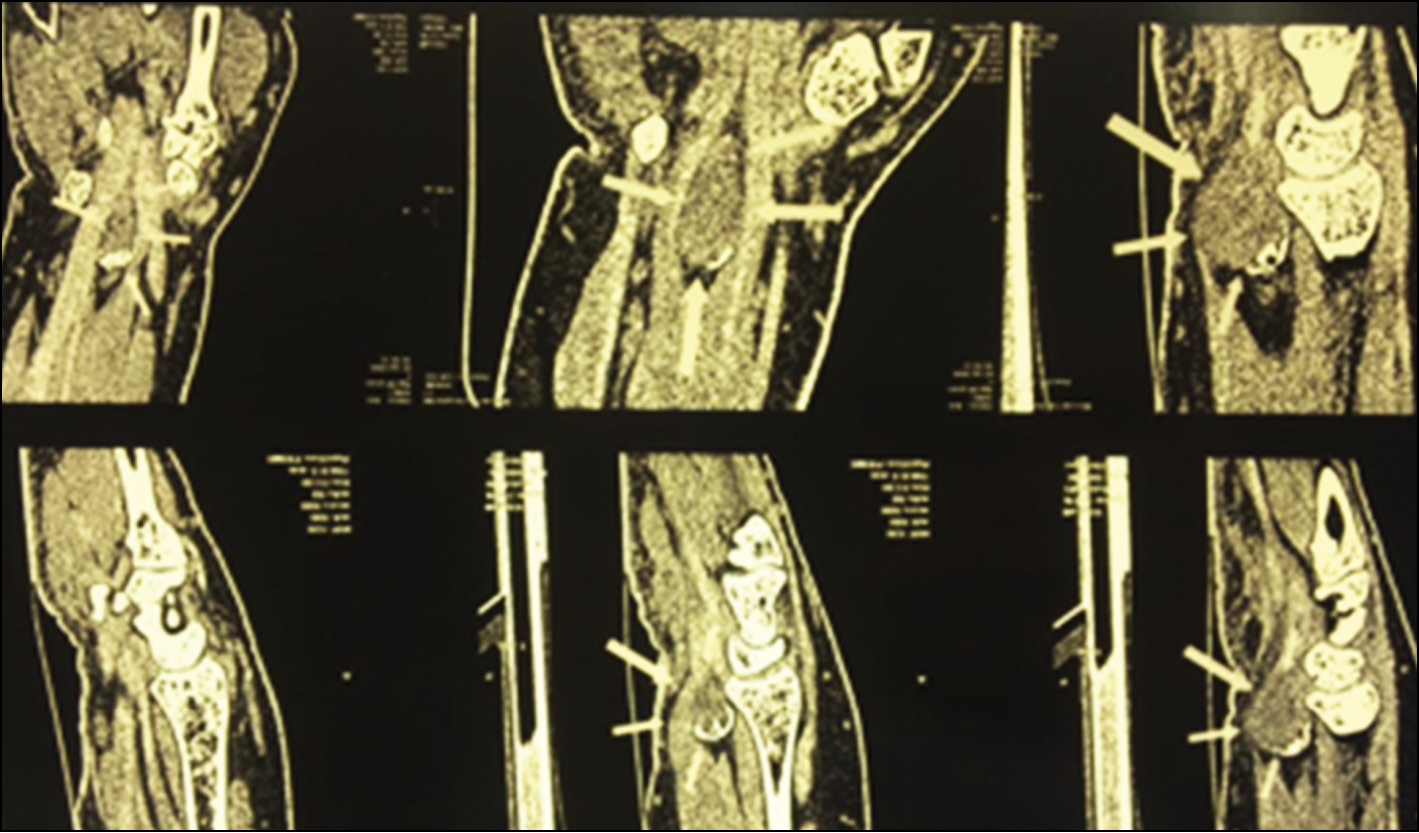

Ангиография использовалась при диагностике опухолей (13 случаев), в которых преобладал сосудистый компонент, для уточнения локализации опухоли, её размеров и взаимоотношения с близлежащими тканями, что важно для определения тактики и объёма оперативного вмешательства. Прямыми признаками опухоли являлись наличие гиперваскуляризации, контрастирование опухоли или её пазух (рис. 9), косвенными — смещение магистральных сосудов и реже — сужение их просвета. Эти признаки встречались как в отдельности, так и в сочетании.

Рис. 9. Контрастирование сосудистых пазух опухоли.

Fig. 9. Contrast vascular sinuses of the tumor.

КТ помогала при выявлении новообразований костей кисти (рис. 10). Однако она играла свою роль также и в выявлении участков минерализации и костных включений в опухолях мягких тканей кисти, периостальной реакции.

Рис. 10. КТ: гигантома, исходящая из сухожилия-сгибателя III пальца.

Fig. 10. CT: gigantoma of the flexor of the third finger.

КТ кисти проводилась 15 пациентам с целью выявления участков минерализации костных включений при ДОМТ кисти.